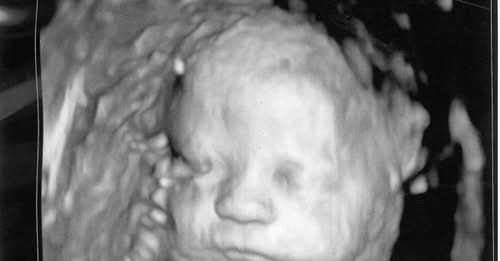

In addition, the sweeping Constitutional Amendment would end protections against brutal late-term abortions, upending our time-tested Pennsylvania law. The Amendment would mean abortion up to the moment of birth. Under current law, babies of six months’ gestation and older are protected from abortion, except in the rare cases where the life of the mother is at stake or the pregnancy would result in irreversible impairment of a major bodily function.